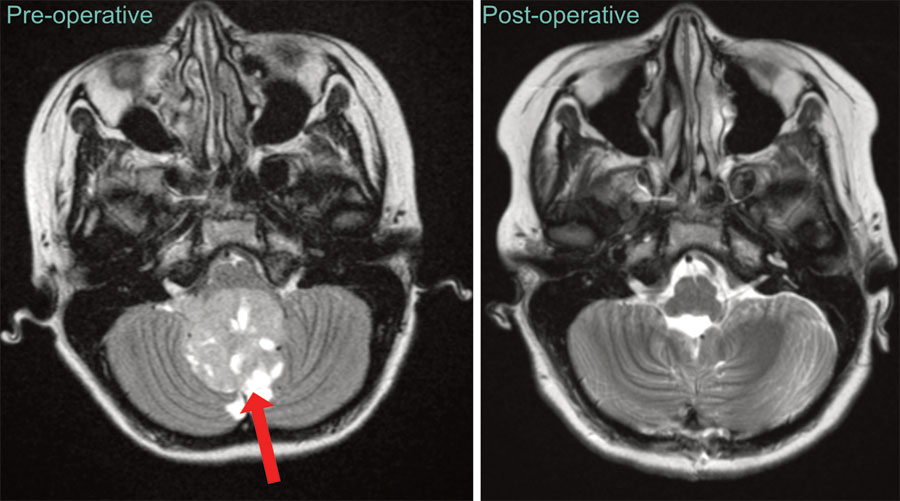

Being one of the world’s top research institutions, patients have access to world-renowned experts and state-of-the-art clinical research trials. We are committed to serving all children with pediatric brain and spinal cord tumors, even if treatment has been initiated elsewhere. Surgery is usually the first, and often most critical step in treating children with brain and spinal cord tumors. In addition to our exceptional experience in complex brain tumor surgery, we offer expertise in minimally invasive techniques, including endoscopy, laser interstitial therapy, and keyhole approaches. which allows us to safely and effectively treat tumors in difficult-to-access areas. When employed judiciously, these minimally invasive techniques serve to greatly reduce post-operative recovery time.